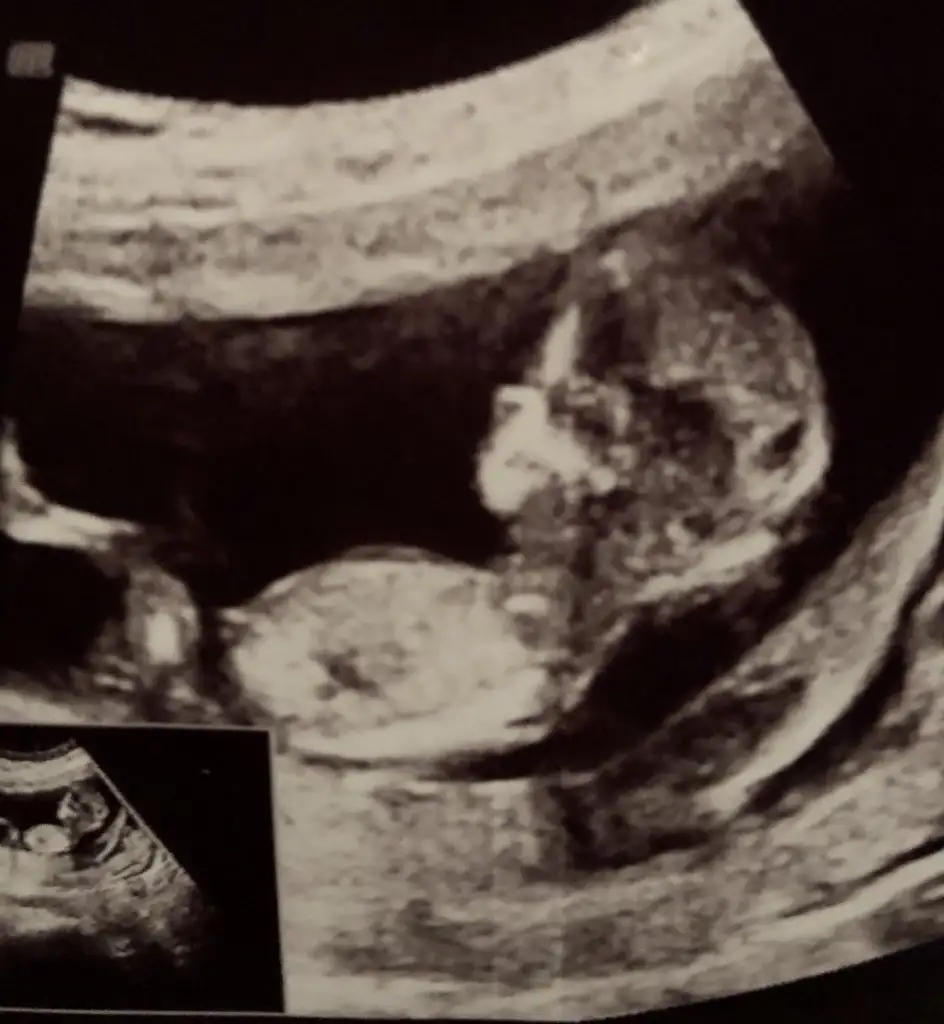

dr soylemeden siz gorun genital nub teorisi ( bebegin cinsiyeti)

Banada erkek gibi dedi bakalim bilebilcek mi ogrenince hemen yazalim genelde hep biliyo😍

14+3 de dedi erkek diye